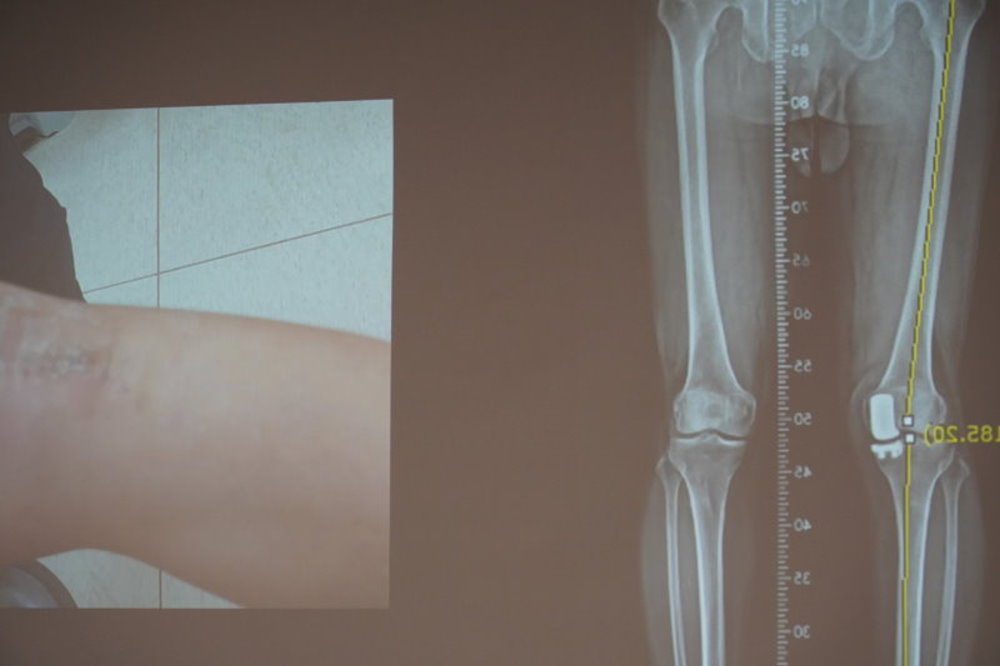

成大醫院骨科部張志偉醫師為蘇先生安排X光檢查後發現,左膝已出現晚期關節病變——上下骨頭相「貼合」且下肢內翻變形。蘇先生在起身和下樓時,因膝關節無法承受突然增加的重量,而產生明顯疼痛、無力甚至軟腳。由於疼痛難忍,蘇先生決定接受手術以恢復日常生活。全膝關節置換手術為常見的安排,所幸蘇先生的病變侷限於內側,經詳細討論後,他選擇以微創方式進行單腔室人工膝關節置換,手術當天下午就能站立及行走,3日後出院,不到2個月就不需助行器輔助,恢復正常活動。

張志偉醫師進一步說明,單腔室膝關節置換常見結構為金屬股骨髁元件、超耐磨聚乙烯墊片及脛骨元件組成,針對關節嚴重病變部位進行置換,大範圍保留原生結構。配合成大醫院關節置換團隊的微創技術與疼痛控制,術後疼痛大幅減少,加快康復,許多患者第一次回診時,僅需單手拄拐(杖)即能自由行走。